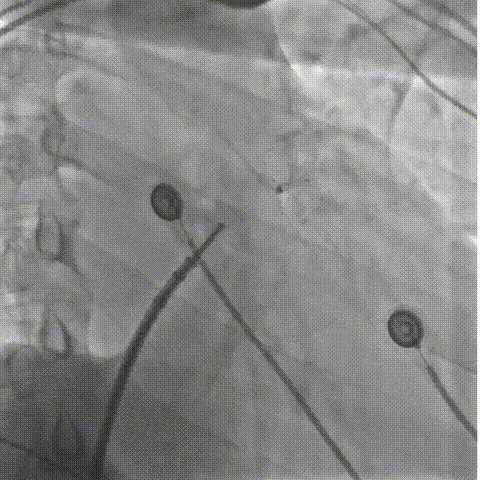

LAMax LAAC® 2430 Normal封堵器封堵盘在DSA下牵拉15s,锚定伞稳定无移位。

牵拉实验

符合COVER原则,将LAMax LAAC® 2430 Normal封堵器释放,再次DSA造影检查,封堵器形态无变化,封堵效果好。

释放后造影